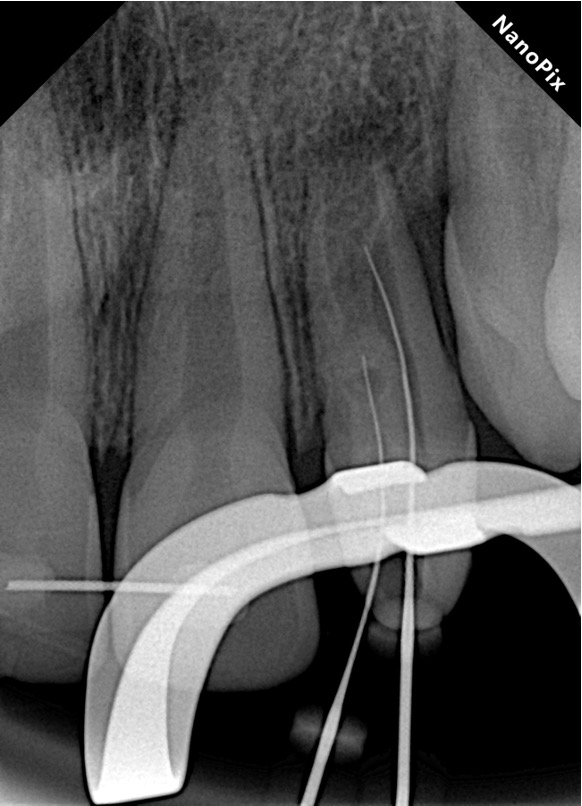

Endodontia Regenerativa

Uma modalidade relativamente recente para tratamentos de dentes com rizogênese incompleta. Mesmo aqueles dentes que já apresentam necrose pulpar e lesão periapical podem ser tratados através da revascularização pulpar, onde o canal radicular é preenchido com coágulo sanguíneo a fim de induzir a continuação da formação radicular tornando o dente mais resistente às cargas oclusais.